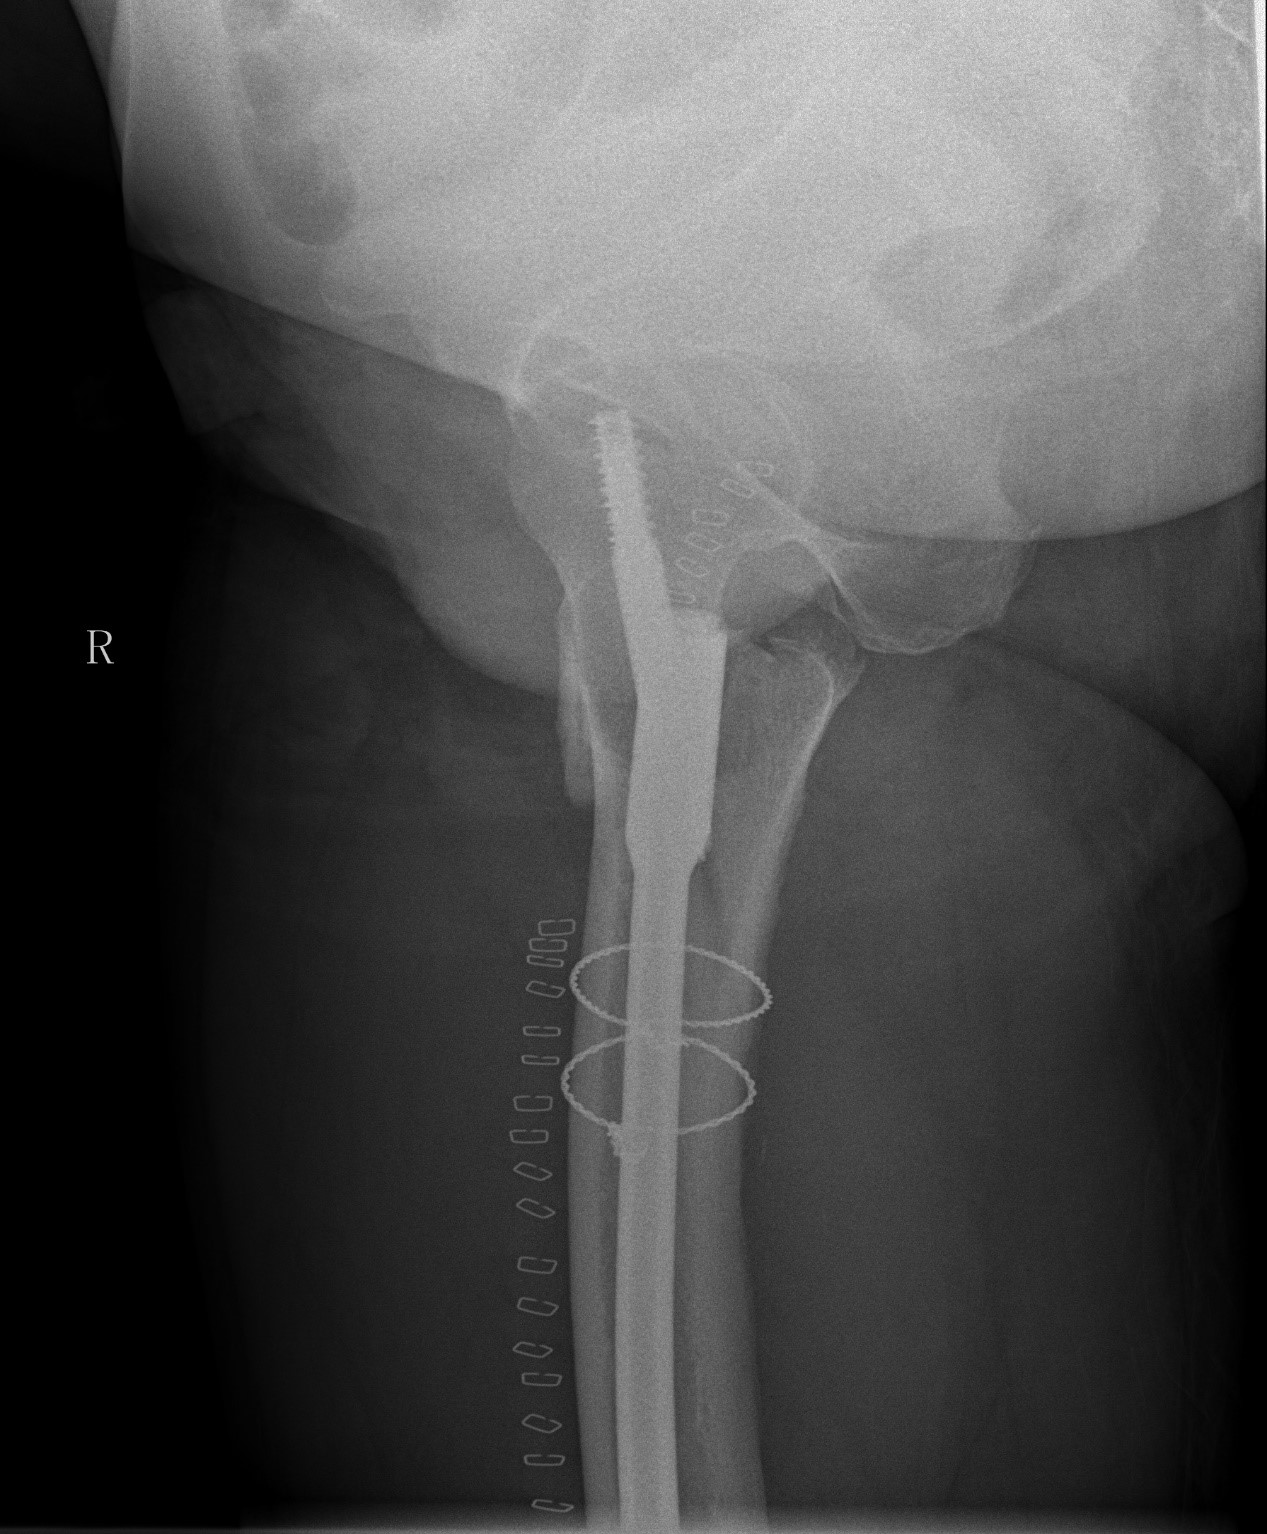

案例一:82岁女性术后再摔伤

患者情况:熊奶奶,一个月前在我院因右髋骨折接受髓内针内固定术,术后康复中因不慎摔倒,再次出现右髋部疼痛并活动受限。经检查,确诊为股骨骨折。患者伴有帕金森病和高血压,身体状况较差。

摔倒原因分析:

术后康复期内,下肢肌力不足;

气温降低,衣物增厚,导致活动灵活性下降。